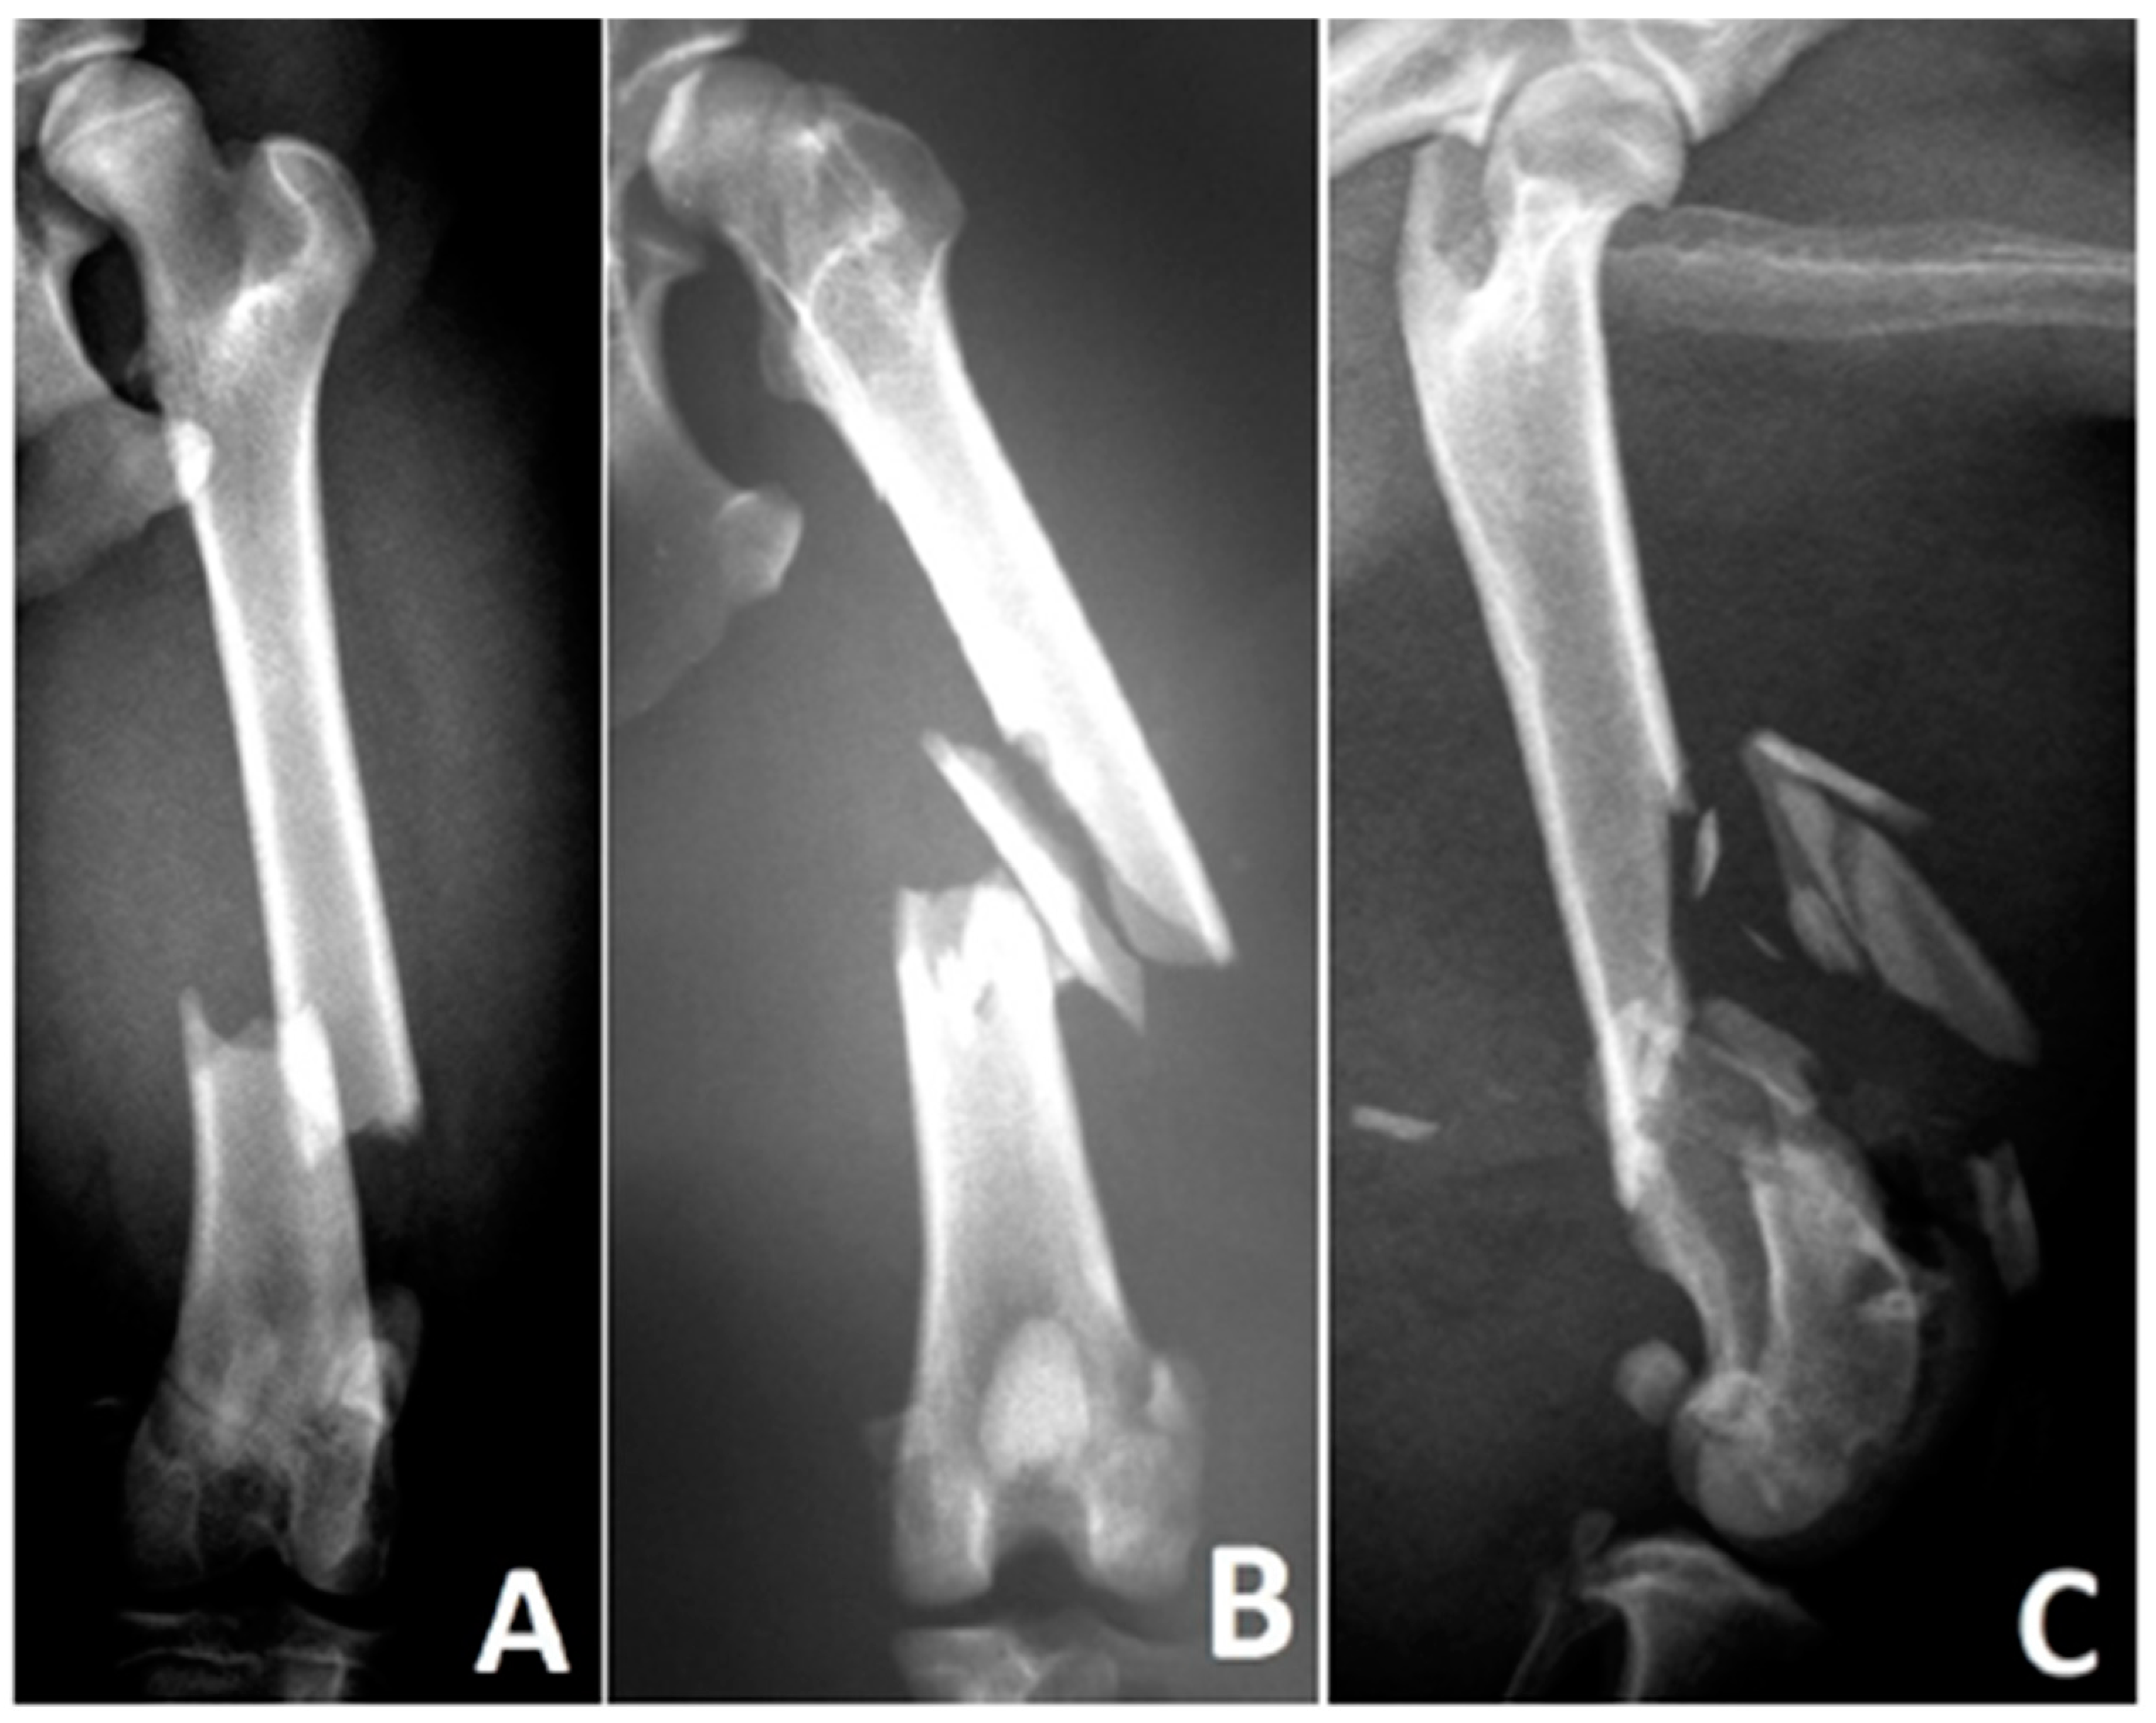

Figure 3. Types of diaphyseal fractures in a canine femur—(A) simple fracture, (B) wedge fracture, (C) complex fracture, according to Unger et al. (1990) 6.

(Figure 3)

ASimple (single fracture line, bone defect ≤ 1/3 of the bone diameter)

BWedge (isolated fragments, fragments maintain contact after reduction)

CComplex (isolated fragments, no contact between fragments after reduction)